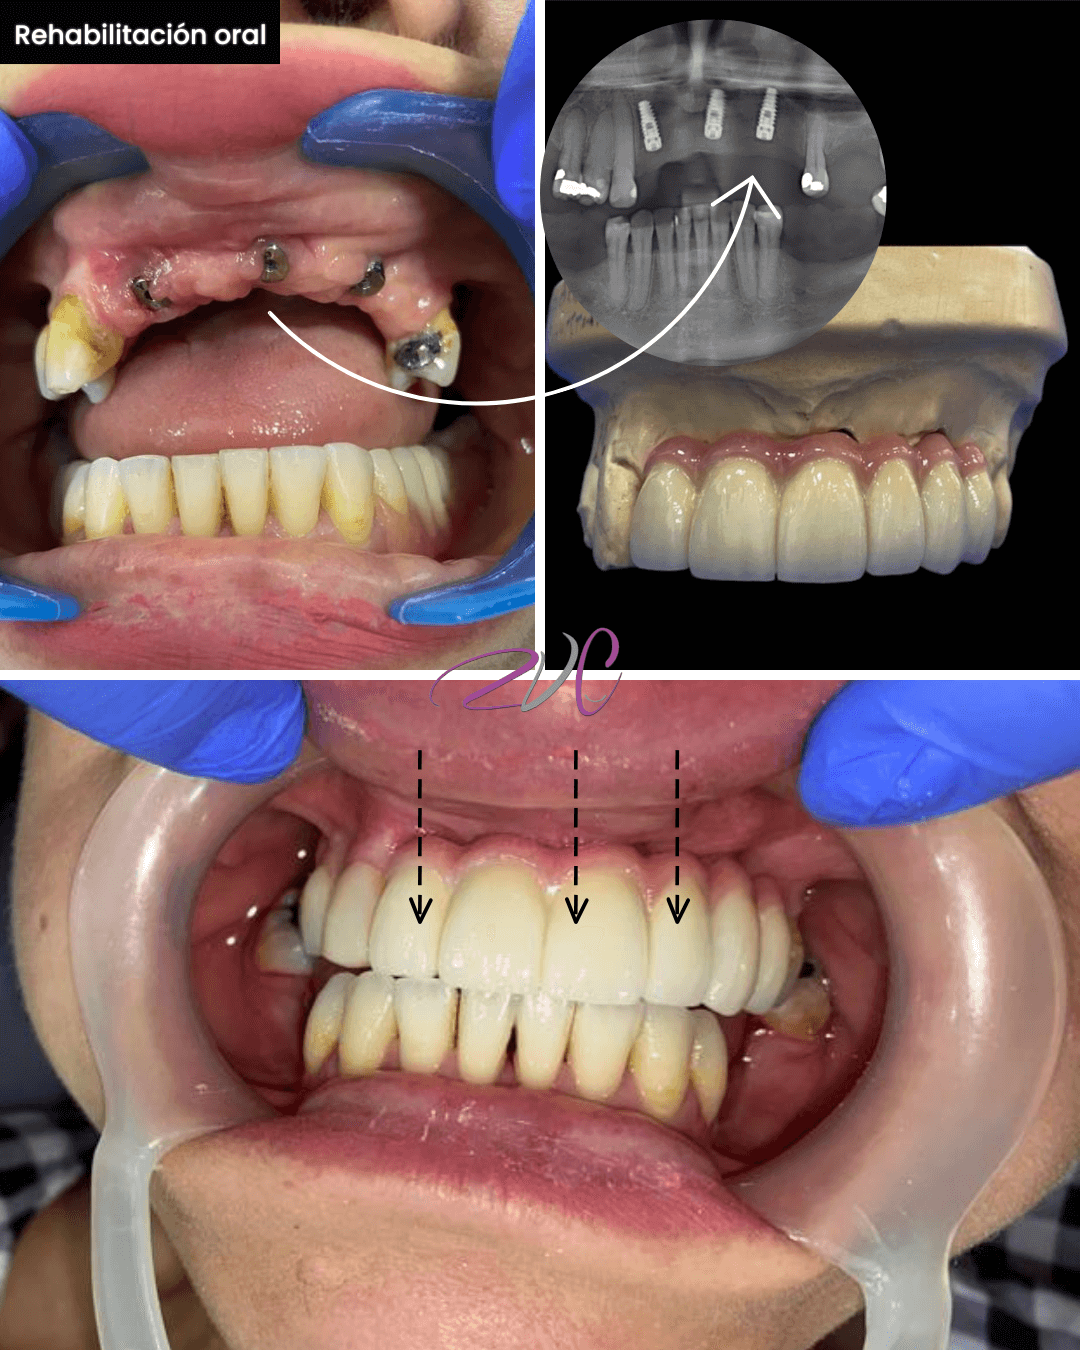

Rehabilitación Oral

Especialidad enfocada en restaurar la funcionalidad y estética de la boca cuando se han perdido dientes o estructuras dentales. Incluye tratamientos como coronas, puentes, prótesis fijas o removibles e implantes dentales. Ideal para devolver salud, estabilidad y confianza al paciente.